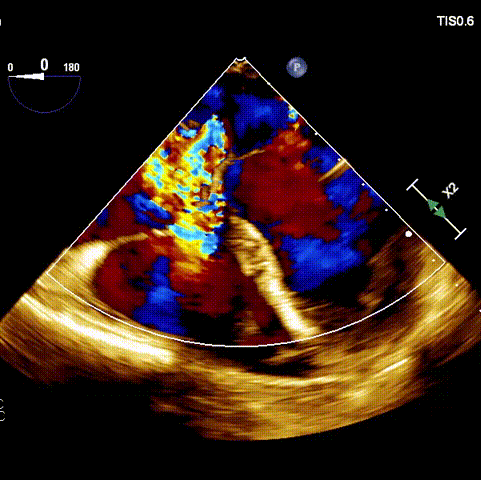

術前超聲

接受手術的為一名80歲男性,因“心悸2年,氣喘伴下肢水腫半年”入院。超聲心動提示“極重度三尖瓣反流,右房及右室明顯擴大,右心收縮功能輕度減低,左心收縮功能正常,肺動脈壓力正常”。患者同時合并有“持續性房顫”及“慢性心力衰竭”,病史持續2年,規律口服抗凝及強心、利尿治療治療效果不佳,癥狀持續。經廈心心臟團隊評估后,認為患者三尖瓣極重度反流并伴有心衰表現,長期內科藥物治療效果不佳,且患者高齡、外科手術風險高,因此決定采用微創經頸靜脈LuX-Valve Plus三尖瓣置換系統為患者治療。

術前經過全面系統的評估后,考慮患者存在高齡、心功能減低、三尖瓣瓣環重度擴張(三尖瓣極重度反流)等高危因素,因此廈心結構心團隊聯合超聲心動、麻醉及護理團隊,制定了詳盡的圍術期治療方案及術中治療難點預案。術中,由王焱院長主刀,在蘇茂龍主任超聲心動團隊的輔助,上海市第一人民醫院陸方林主任的協助下,僅用時30分鐘,即順利完成了三尖瓣原位置換的手術。術中患者血流動力學穩定,術后即刻顯示LuX-Valve Plus瓣膜位置良好,固定穩定,瓣膜功能正常,無瓣周漏。

術后超聲